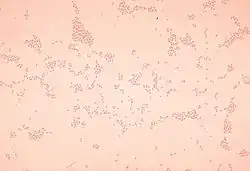

Actinobacillus

Actinobacillus is a genus of Gram-negative, nonmotile and non-spore-forming, oval to rod-shaped bacteria occurring as parasites or pathogens in mammals, birds, and reptiles.[1] It is a member of the family Pasteurellaceae.[2] The bacteria are facultatively anaerobic or aerobic, capable of fermenting carbohydrates (without production of gas), and of reducing nitrates. The genomic DNA contains between 40 and 47 mol % guanine plus cytosine.